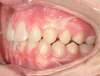

Cas 2 : Description

Tendance prognathisme.Traitement par gouttières.

Avant

Après